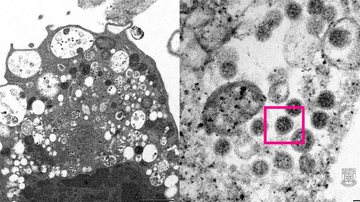

Faculdade de Medicida de Hong Kong

"Infelizmente, sim, a ômicron está gerando hospitalizações e, infelizmente, pelo menos um paciente teve a morte por ômicron confirmada", disse Johnson.  |   Bnews - Divulgação Faculdade de Medicida de Hong Kong